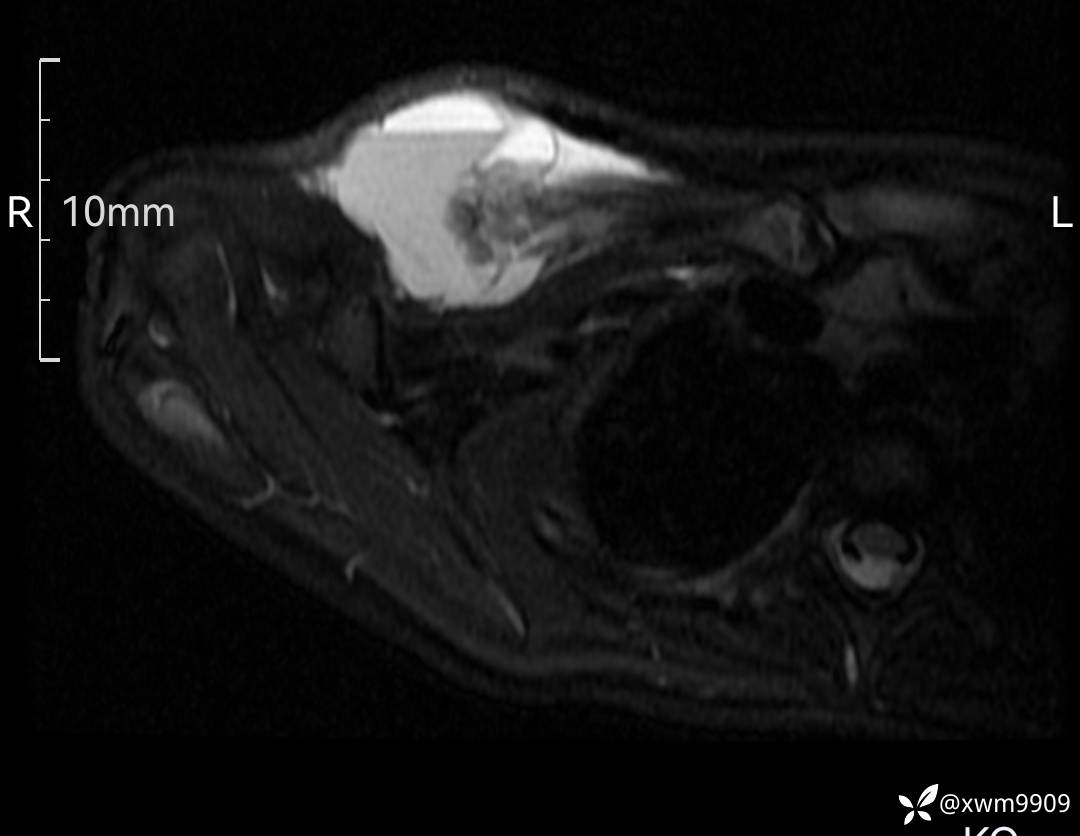

3、查体,右锁下方可及一约5x6Cm肿物,软丶边清丶未见明显发红,肤温不高,压痛明显,不可推动,稍有波动感。其他无特殊。

2、CT、MR肿块内可见液-液平面,常见有哪些疾病。